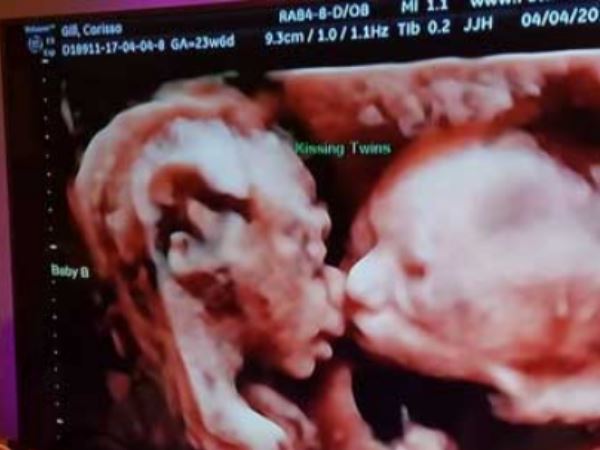

नई दिल्ली। जुड़वा बहनों की गर्भ में प्यार करते हुए एक तस्वीर सबका दिल जीत रही है। अल्ट्रासाउंड मशीन से ली गई ये तस्वीर खूब वायरल हो रही है। इस तस्वीर को फेटल विजन ने इंस्टाग्राम के पेज पर शेयर किया है।

एनडीटीवी की खबर के मुताबिक, ये तस्वीर पेंसिल्वेनिया के क्रॉयडन में रहने वाली महिला कैरिसा गिल के गर्भ में पल रहे जुड़वा बच्चों की है। गिल 24 सप्ताह से गर्भवती हैं। वह 11 अप्रैल को रूटीन चेकअप के लिए डॉक्टर के पास गईं थी, जब उनका अल्ट्रासाउंड किया तो जो तस्वीरें आईं उन्होंने दुनिया का ध्यान अपनी ओर खींच लिया है।

अल्ट्रासाउंड में पता चला कि उनके गर्भ में जुड़वा बच्चे पल रहे हैं। इन जुड़वा बच्चों का आपस में प्यार की तस्वीर भी अल्ट्रासाउंड मशीन में कैद हो गई। इन बच्चों की किस करते ये तस्वीर सोशल मीडिया पर खूब पसंद की जा रही है। डॉक्टर के मुताबिक ये दोनों लड़कियां हैं।

कैरिसा गिल ने कहा कि मैं अपने गर्भ में पल रहे बच्चों का प्यार देख खुशी से रो दे रही हूं। उन्होंने कहा कि मैं इनका नाम इसाबेला और कैली रखूंगी। गिल ने कहा कि मां बनना एक खास अहसास है और अपने बच्चों की तस्वीर ने तो इसे और भी खूबसूरत बना दिया है।